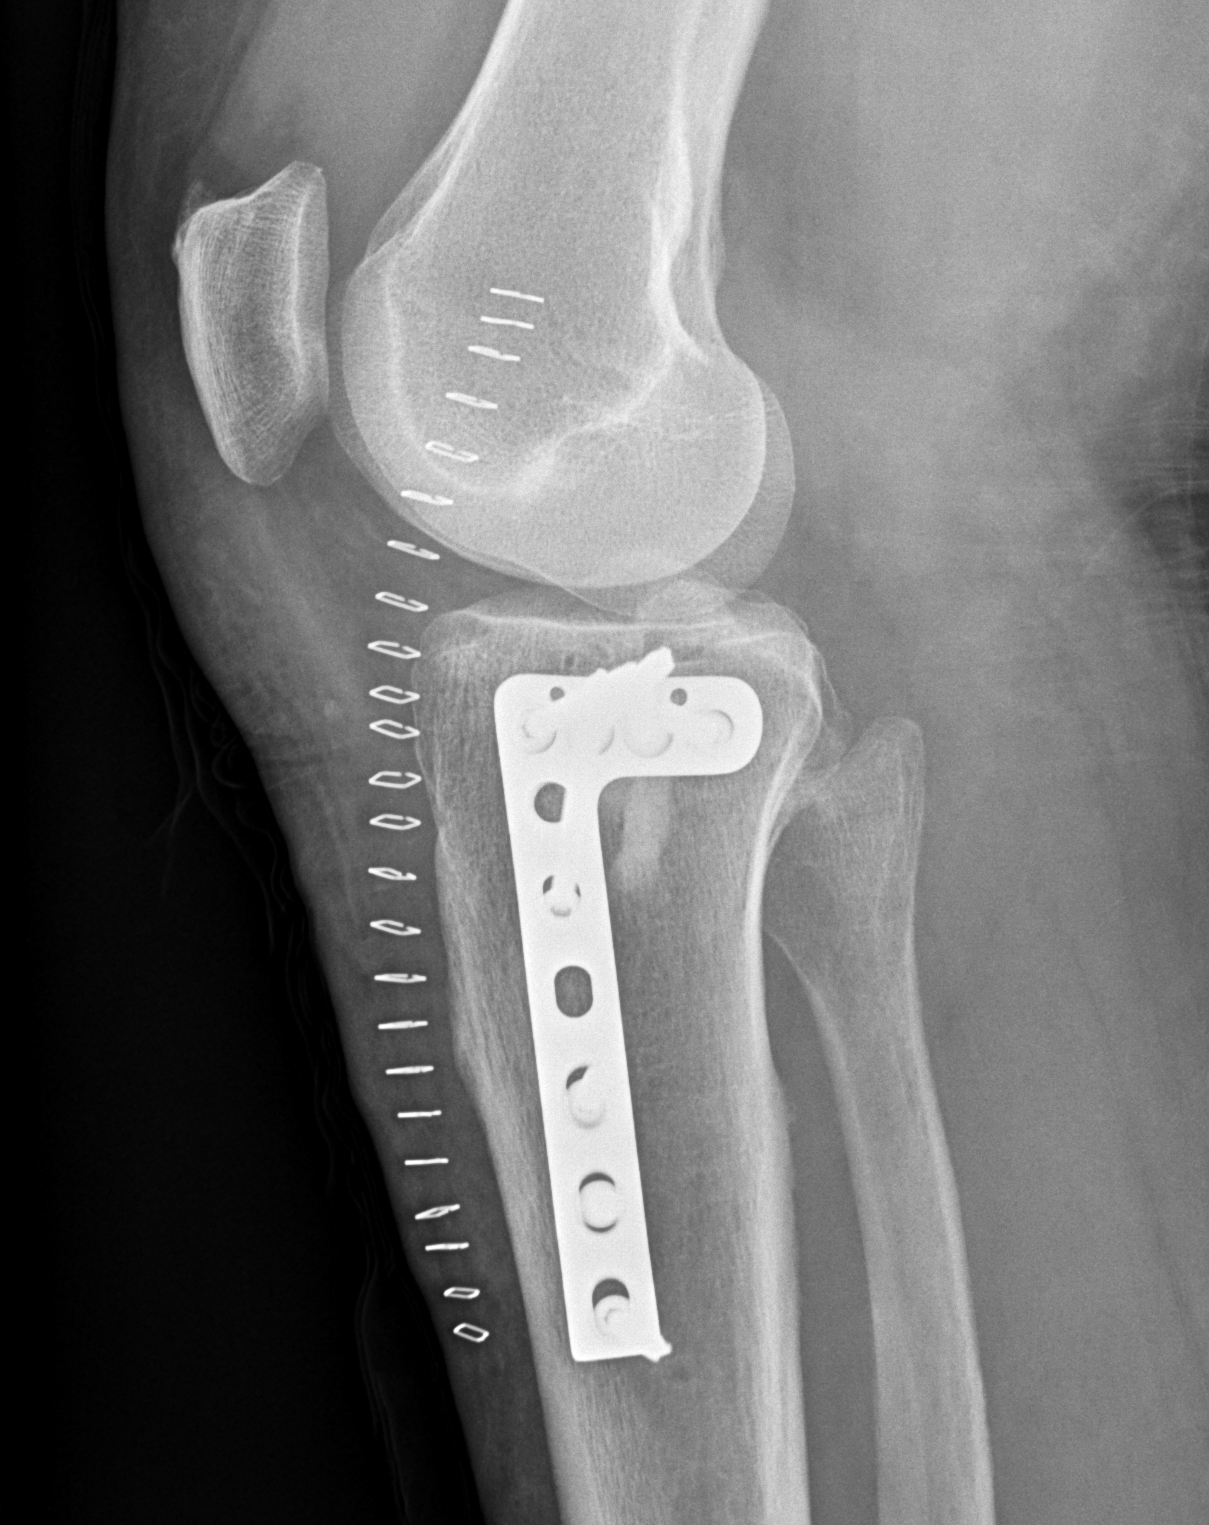

1. Medial and Lateral Plating

Technique

- depends on which of the three columns affected

- anterolateral approach for lateral column

- posteromedial appraoch for medial / posterior column

Type VI Bicondylar with Metaphyseal Fracture

- long locking plate minimally invasive with locking jig / MIPO

- proximal lag screws

- ensure correct alignment

- often use small medial buttress plate